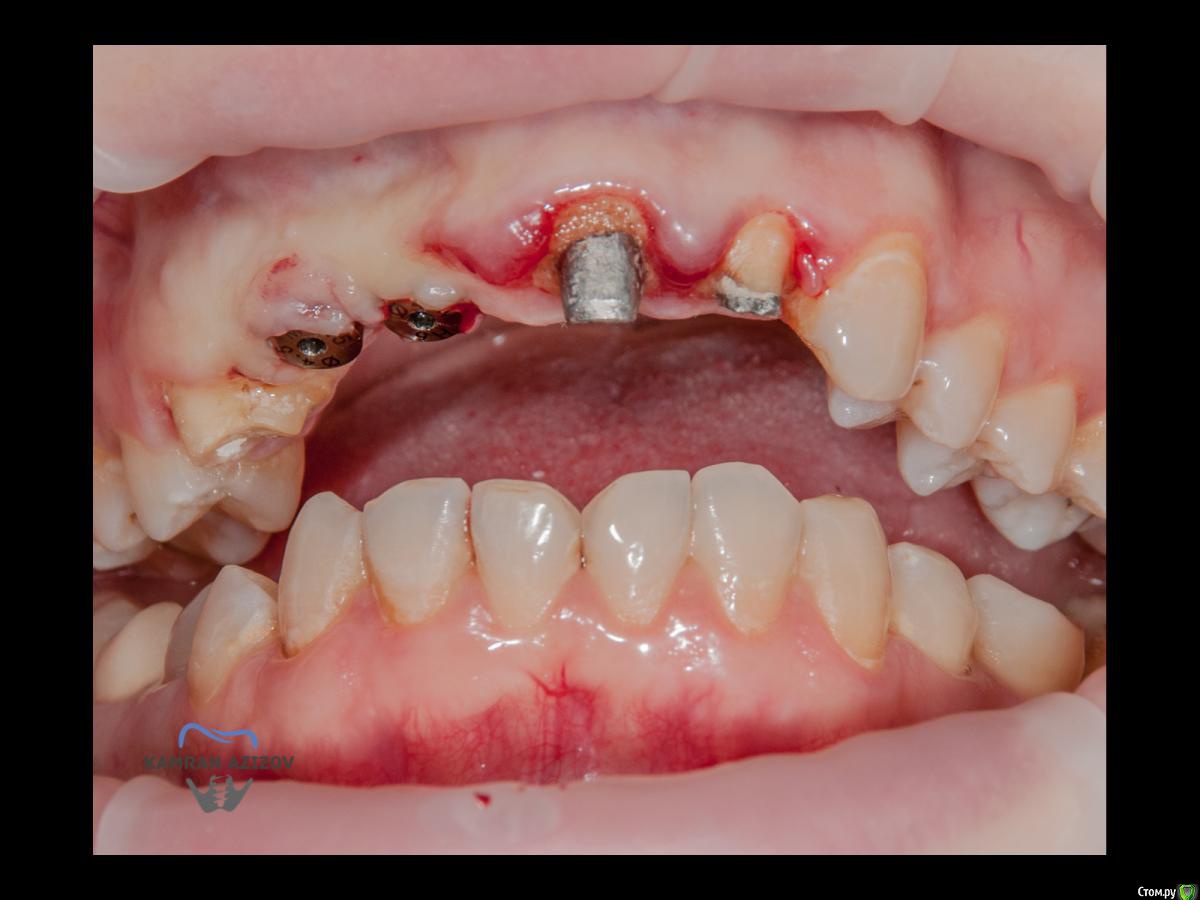

kamranchick Опубликовано 6 апреля, 2019 Поделиться Опубликовано 6 апреля, 2019 (изменено) Хай Гайсдавно ничего не комментировал и не выкладывал, что то настроения не было, да и муза не посещалаСитуация следующаяпришла пациентка, жалобы на неприятный запах из рта, сначала не понял что за хрень, ну как распилил мост понял че к чему... халтура.Ну и по кейсуУдаление клыка и 2ки, через 2 месяца навигация, имплантация + Шашлыки по карлоссу, смена формиков, временное протезирование. только мягкие ткани, Изменено 6 апреля, 2019 пользователем kamranchick 7 1 Ссылка на комментарий

АнтонТЛТ Опубликовано 6 апреля, 2019 Поделиться Опубликовано 6 апреля, 2019 Чё то двойку слишком небно запилил 2 Ссылка на комментарий

kamranchick Опубликовано 6 апреля, 2019 Автор Поделиться Опубликовано 6 апреля, 2019 Ориентировались тут в основном по кости... Ссылка на комментарий